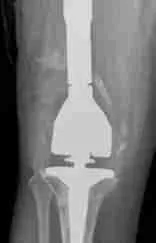

Revision Total Knee Replacement Surgery

Sometimes the implant can become loose. It is not always clear what may lead up to a loose implant. Orthopedic surgeons believe that repetitive high-impact activities, high body weight, and wear of the plastic liner may lead to quicker wear of your knee replacement, leading to implant loosening. Patients who undergo a knee replacement at a younger age are at a high risk of having their knee replacement become loose.

Loosening occurs when the tiny particles generated when the plastic liner wears out is attacked by your body’s immune system. The immune system then destroys the healthy bone around the implant. This bone destruction is called “osteolysis”. When osteolysis occurs, the implants can begin to have a windshield wiper movement and become loose, causing pain.

A revision total knee requires extensive preparation. Dr. Morton will require your previous medical charts, x-rays, and other imaging. Sometimes before surgery, he will order more advanced imaging such as a CT or MRI may be required. You will almost always need laboratory tests to determine if there is an infection in your knee.